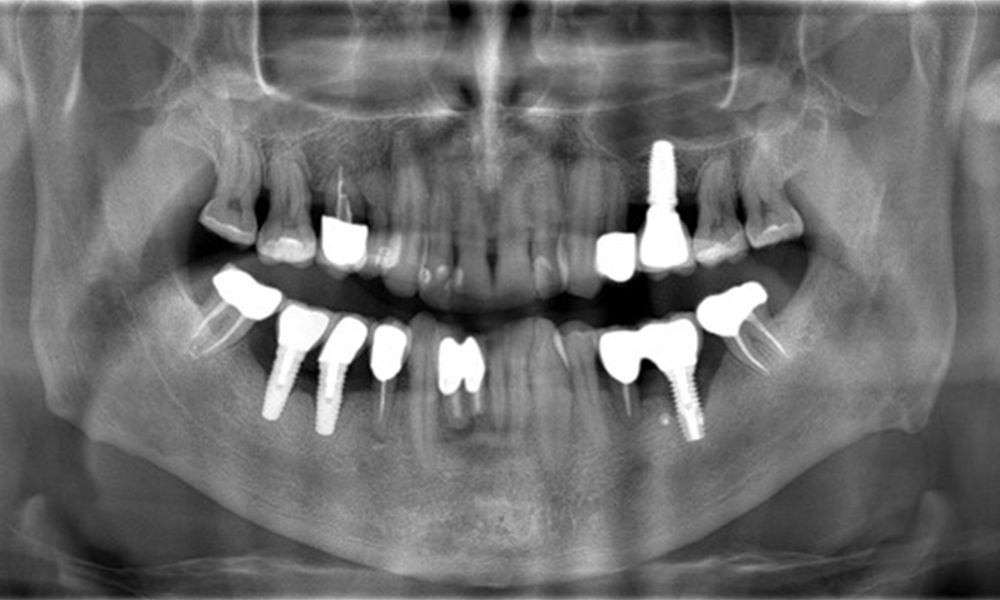

A 52-year-old patient presents at a preventive care session. The patient has no systemic disease and is not taking any medication. He has had various dental treatments and also has two active carious lesions. In addition, the patient has four implants (2nd, 3rd and 4th quadrants). He is revealed to have early periodontal disease (stage IV, grade B). His periodontal condition is stable; a probing depth of Probing depths (ST) of 5 mm is only evident at the implant in region 36. Gingivitis is also identified.

The patient has no particular risk factors with specific dental implications in his medical history. The key factor, therefore, is the requirement in terms of oral health. In this respect, there is evidence of a probing depth of 5 mm at the implant in the 3rd quadrant and, on the X-ray image, increased bone loss. The patient also has currently stable early periodontal disease and two active initial carious lesions.

The X-ray images show the progression of bone loss. OPG from 29.06.2020 (left) and OPG from 26.02.2024 (right).

OPG: 26/02/2024 Dental X-ray: 18/01/2024